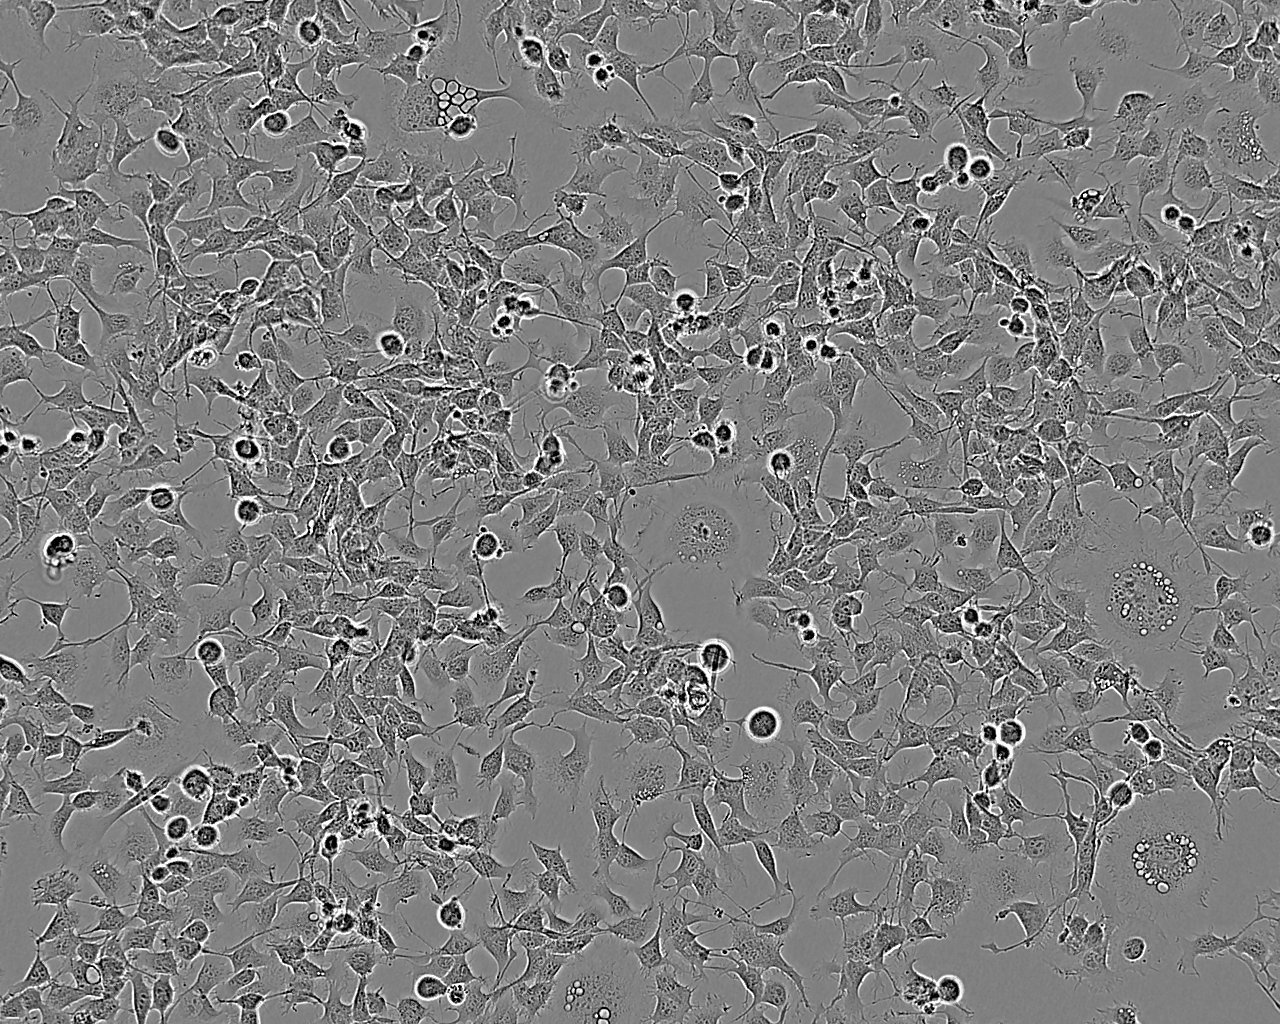

SNB-19 epithelioid cells

细胞形态:上皮细胞样

细胞生长:贴壁

细胞生长特性:贴壁生长